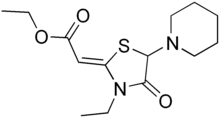

| Formula | C14H22N2O3S |

| Molar mass | 298.40 g·mol−1 |